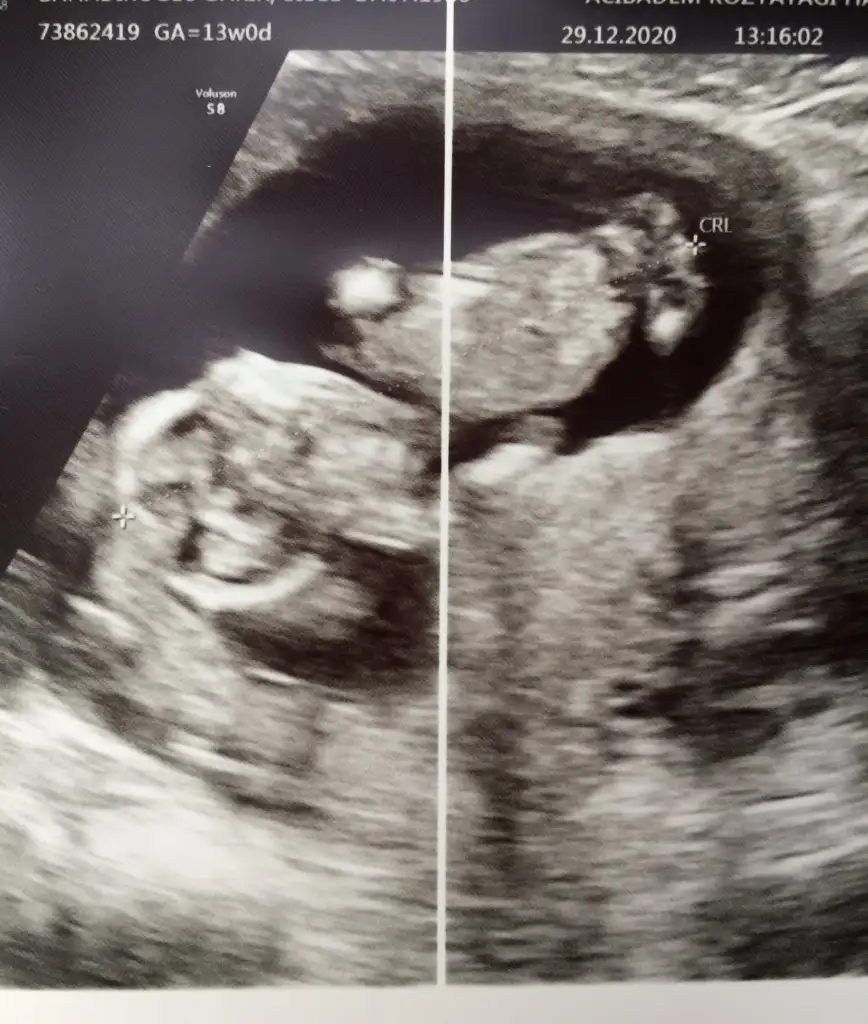

11+3 aslında ama 13te gidersem yine atarım canım 7. Haftaya kız demiştin hadi bakalım sağlıklı akıllı bebisler olsunlar da inşallahBebek baş aşağı yorum nasıl yapacam şaşırdım11 12 13 haftalar olursa paylaşın erkek gibi sanki bir uzantı var nubunda ama olmayabilir

Erkek görünüyorEki Görüntüle 2749723 Eki Görüntüle 2749724 Günaydın ikra meyra buna da bakarmısın 11+3